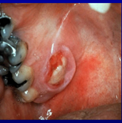

Acute parotitis

A

Ascending infection

oral bacteria - S. aureus

Acute swelling, pain

Pus exudes from ducts

Usually 2^ to dry mouth - radiotherapy, Sjogrens, drug-induced